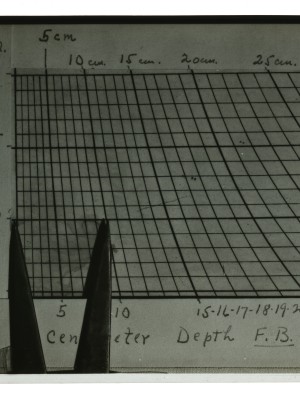

Dr. Edwin Ernst, an only child born to St. Louis residents Charles and Catherine Ernst, was a notable Roentgenologist, a physician who specializes in radiological work. Dr. Ernst studied at Washington University in St. Louis and later at Moravian College in Bethlehem, Pennsylvania earning his advanced degrees. For two years he served as a resident physician at the St. Louis Mullanphy Hospital before leaving to pursue a private practice. When the United States formally entered the war in 1917, Ernst left St. Louis to become chief radiologist at Base Hospital 21. He was discharged honorably in 1919 with the citation of Major. His collection consist of x-ray images taken at Base Hospital 21 as well as drawings of radiological equipment and photographs.